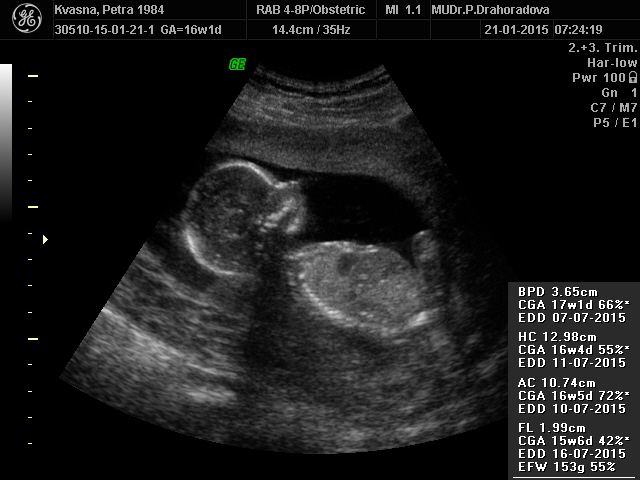

Autor: žirafka84   21.1.2015 v 09:44

ahoj holky,právě jsme se vrátili z kontroly v 16 tt.Brali mi krev na ten tripple test,snad to dopadne dobře.Jinak kontrola super,vše je v naprostém pořádku,zatím,tak snad to tak i zůstane Emotikona smile placenta,kterou jsem měla moc nízko a kvůli které jsem na nemocenské se povytahuje,takže je vše na dobré cestě Emotikona grin mám neskutečnou radost a pocit úlevy Emotikona smile jinak na 80% to bude....holčička, jupííí Emotikona grin mějte se krásně a všem co je čeká kontrola,držíme pěstičky,malá taky